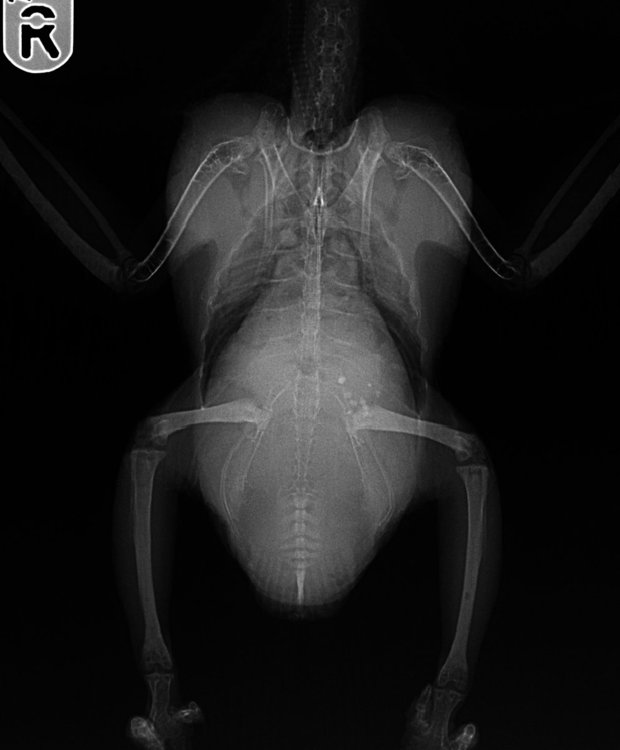

Сделали рентген ( три снимка в приложении ), сдали кровь на анализы ( в приложении ).

Lina_rentgen1.jpg

Lina_rentgen2.jpg

Lina_rentgen3.jpg

Врач высказала предположение, что отек именно сосудистый, так как сосуды сердца атеросклеротические ( видно на рентгене ).